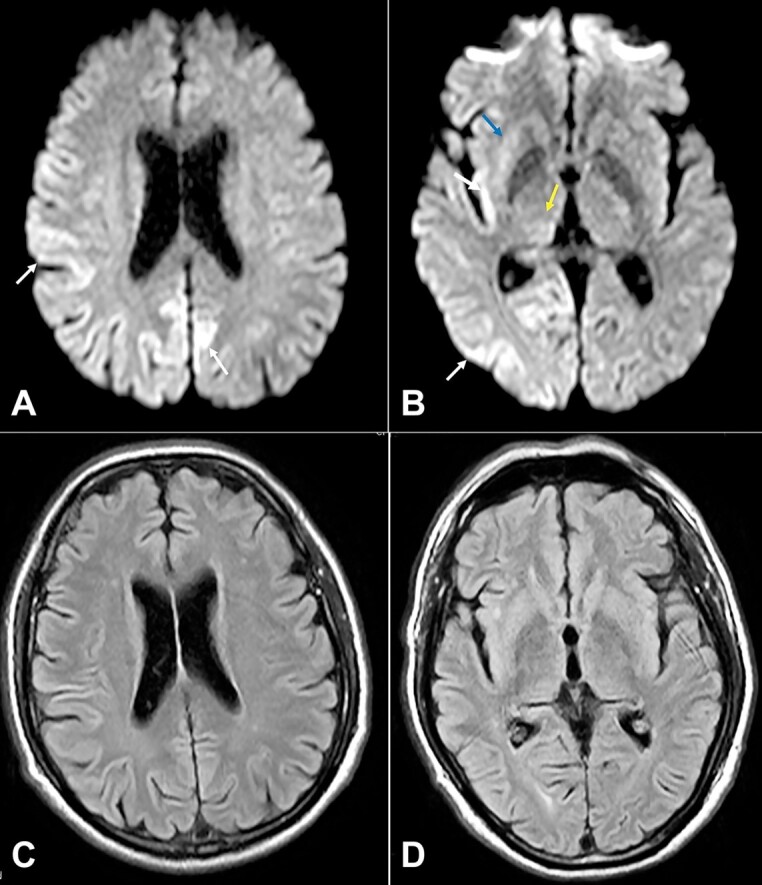

Sporadic Creutzfeldt-Jakob disease (CJD) is a rare neurodegenerative spongiform encephalopathy that causes neuronal derangement secondary to prion protein. Its initial diagnosis is often complex and challenging due to non-specific clinical presentation, lack of awareness, and low clinical suspicion. This disease is invariably fatal, and most patients die within 12 months of presentation. Definite diagnosis of prion disease requires neuropathological analysis, usually done at autopsy. Here, we present the autopsy findings of a 57-year-old male patient, illustrating the complexity of diagnosing this disease early in the clinical course and the need for a broad differential diagnosis at the onset.